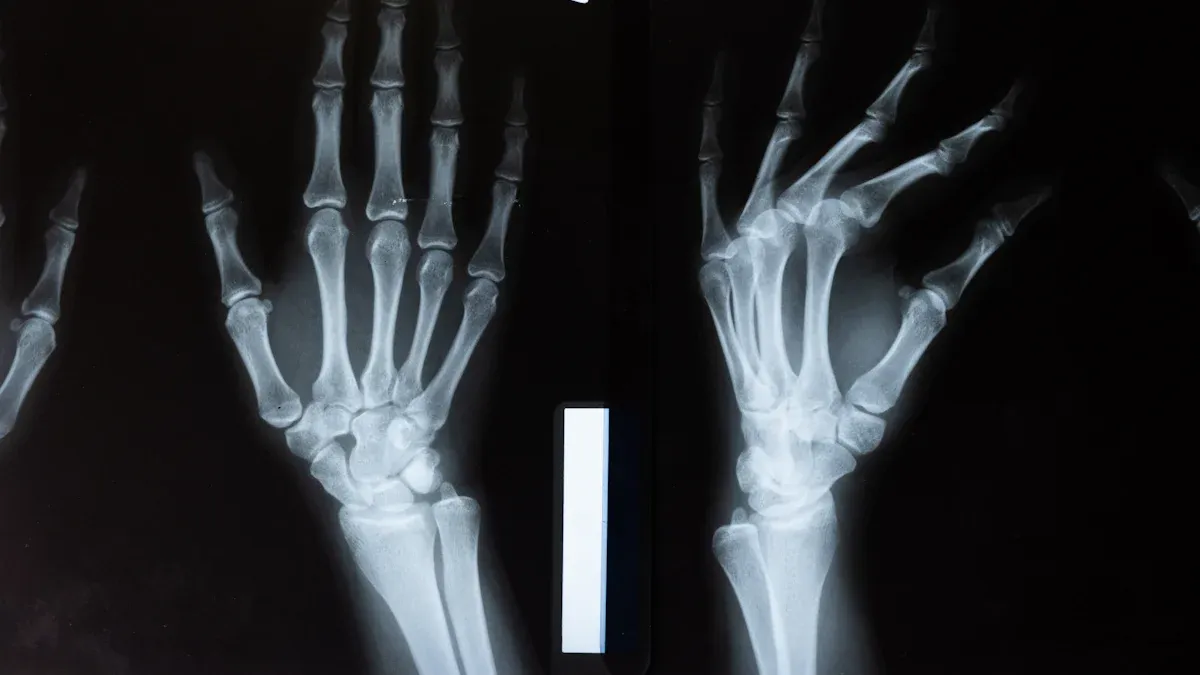

Evaluation

Your first visit starts with a full checkup. The chiropractor asks about your health and listens to your symptoms. You get a physical exam. Sometimes, the doctor uses X-rays to look at your neck. This helps your chiropractor see if your upper cervical spine is not lined up right. The goal is to find out why you feel dizzy or have balance problems.

- You might get imaging tests to check your spine.